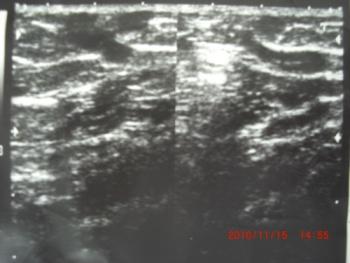

エコーにて交通枝確認